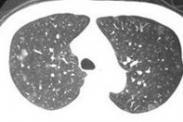

• 急性侵襲型肺曲霉病

628健康網為您分享有關急性侵襲型肺曲霉病的癥狀,急性侵襲型肺曲霉病的治療方法,急性侵襲型肺曲霉病的預防知識,急性侵襲...